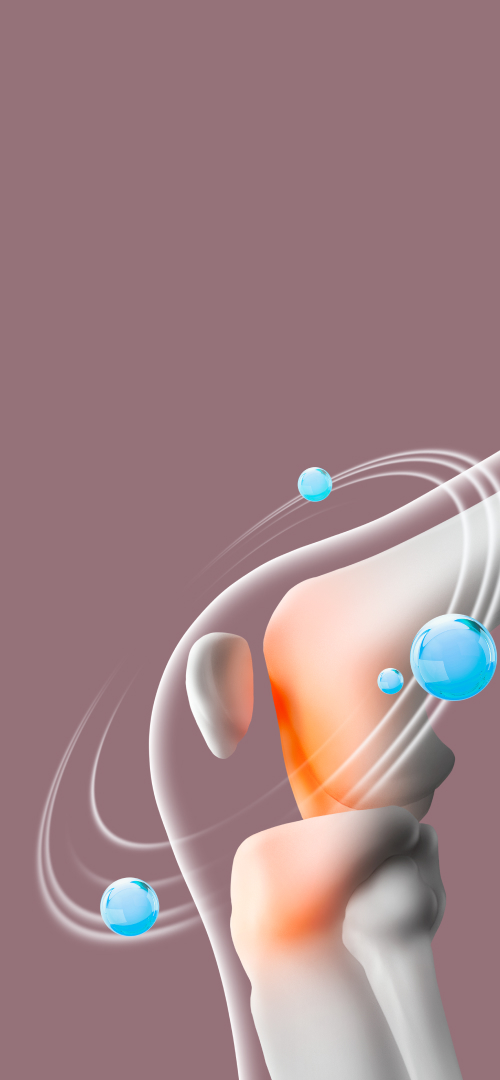

04

힘줄과 뼈의 충돌로 인한 통증

어깨를 많이 사용하는 골프나 헬스, 배드민턴, 테니스 등의 운동을 많이 하는 경우 어깨 부위 힘줄이 어깨 지붕의 뼈와 부딪혀 염증이 생겨 통증이 나타날 수 있습니다.